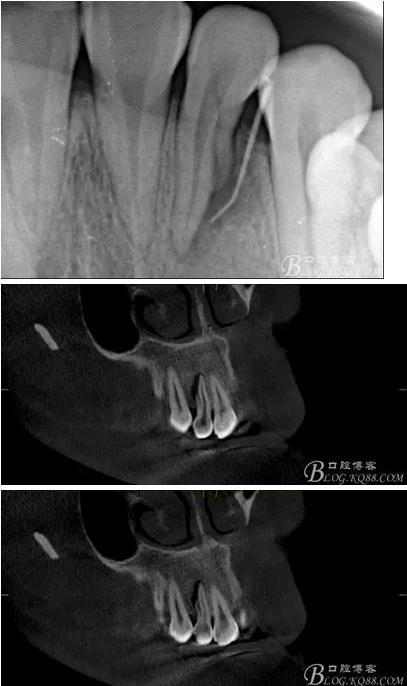

(6)復診:原暫封材料再位,牙周無明顯異常與不適,常規(guī)清潔根管,H銼清除根管內(nèi)維他,次氯酸鈉終末消毒,干燥根管,單尖測壓發(fā)充填根管,術后拍片到位。